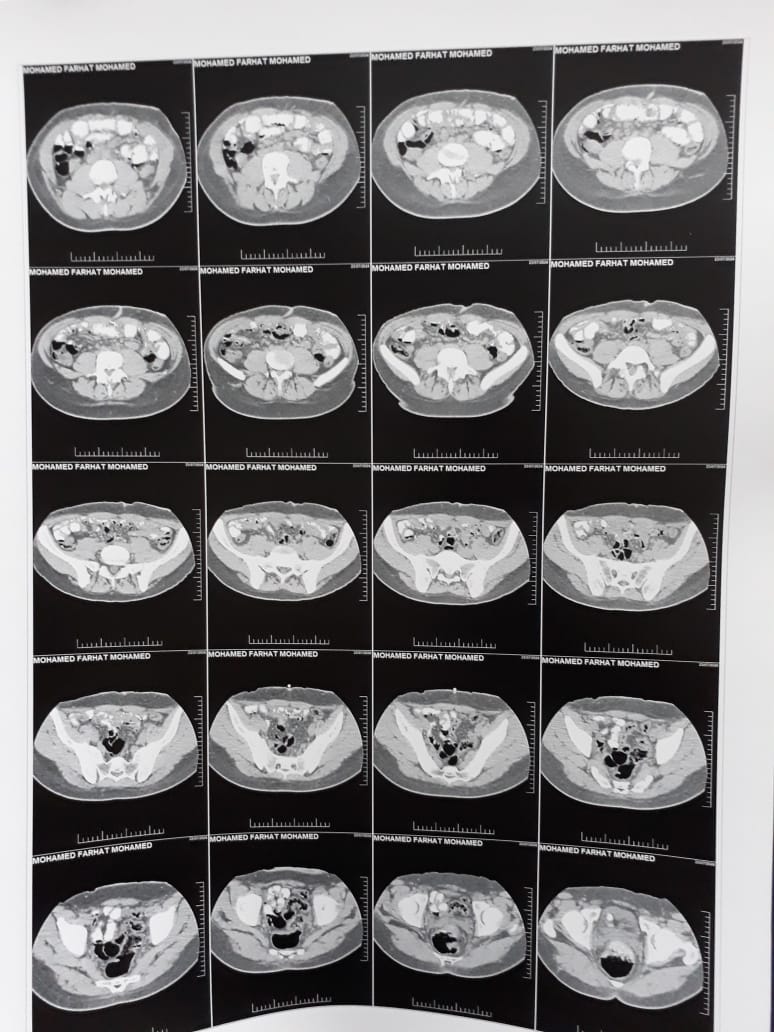

وأكملت: وبعدها رحت بأبني لدكتور تاني، فقالي هو عنده فتق في الحجاب الحاجز وارتجاع في المريء، ومحتاج عملية تحويل مسار، وبعدها عرضت الأشعة على الدكتور عشان يعمله العملية، فقالي ده فتق بسيط، وبعدها رجع في كلامه، بعد ما عرضت الأشعة على مستشفى الجهاز الهضمي، فقالي العملية خطر وهتاخد 8 ساعات، وبالفعل أجرى عملية تحويل مسار في شهر 7 2023، ومن ساعتها وهو تعبان جدا، وعايش على العصير والمحاليل، وكل ما أروح للدكتور يقولي عنده تعب بسيط بس، ولما روحتله تاني قالي هو محتاج عملية خطيرة، وممكن تؤدي إلى الوفاة.

وأشارت والدة محمد فرحات إلى عرض ابنها على طبيب استشاري قائلة: وبعدها عرضت ابني على طبيب مختص، وتبين أن آخر عملية، وهى تحويل المسار التي أجراها الطبيب الأول تمت بشكل خاطئ، وأجمع الأطباء على أنه يحتاج لعملية خطيرة ورفض العديد من الأطباء إجرائها له، وبعدها توجهت للمحافظ ووكيل وزارة الصحة لتقديم الشكاوى، فوافق أحد الأطباء على إجراء العملية، لكن تكلفة العملية بلغت 200 ألف جنيه.